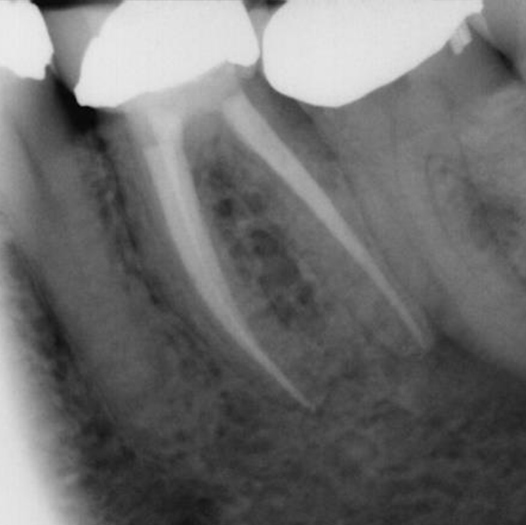

Before

After Root Canal treatment